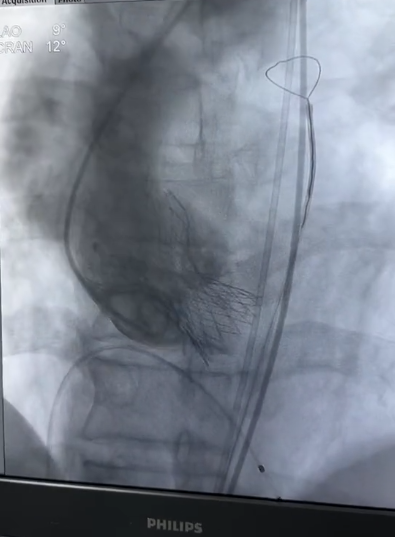

由于患者合并严重肺部疾病,外科开胸手术风险极大,团队经过详细讨论,决定采用经导管主动脉瓣置换(TAVR)手术。术中,针对二叶瓣钙化不均、升主增宽、巨大瓣环、敞口流出道等难点,团队采用 snare 牵引等技术手段,将人工瓣膜精准定位,通过新一代瓣膜支架的「锚定-释放」设计,成功避免瓣膜移位。术后患者症状立即消失。

术后重复造影可见人工瓣膜工作正常,狭窄完全解除,未见明显瓣周漏